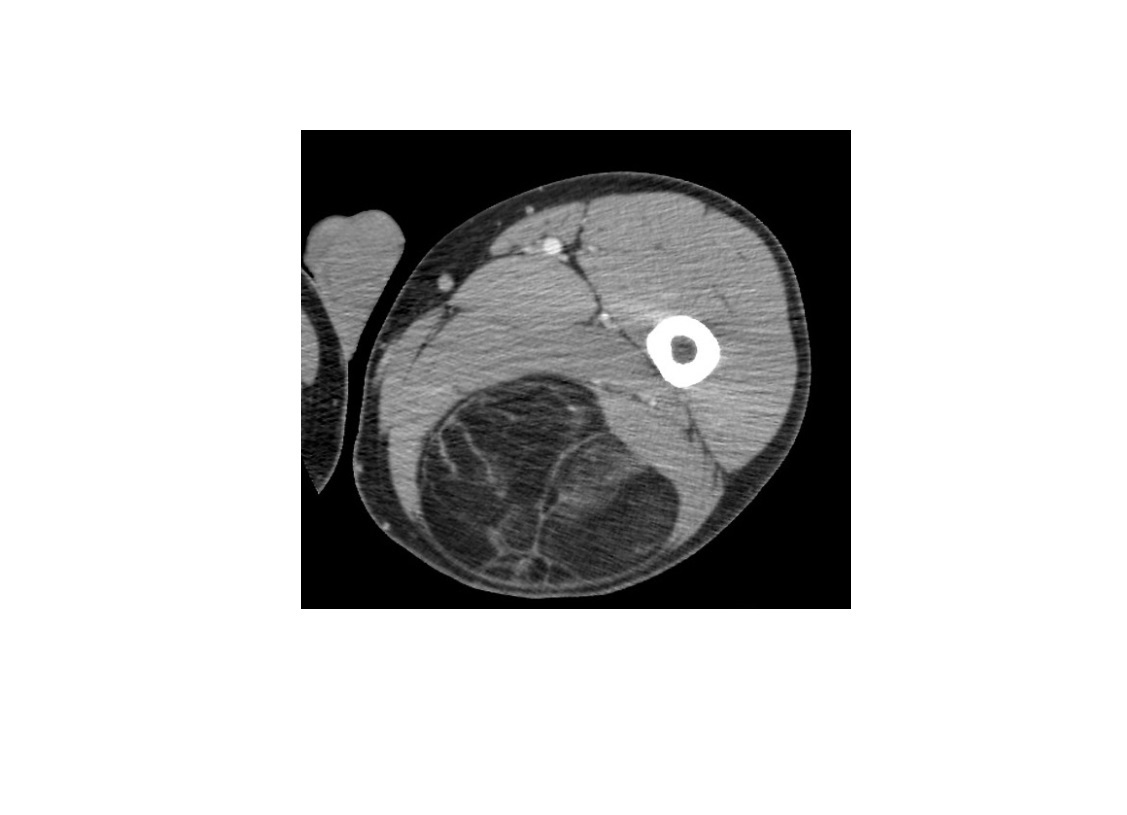

Osteoid osteoma

Cortically based

peripheral sclerosis and central with nidus

**nidus > 2cm = osteoblastoma **

= Posterior elements

Nb** Osteoblastoma can have have soft tissue expansion/involvement**

Double density bone scan

DDx

-stress fracture

- intracortical abscess